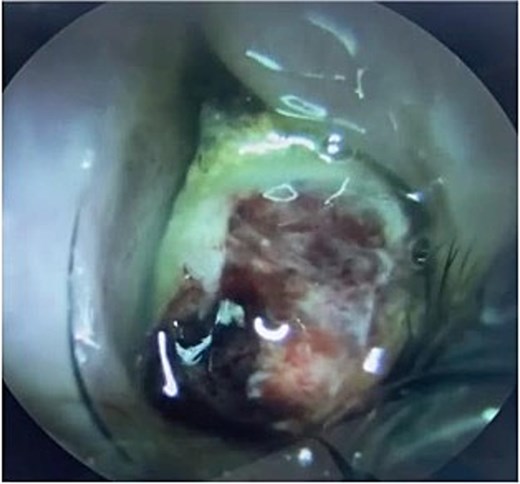

The patient underwent staging CT which was negative for distant metastasis. He then went underwent incomplete medial maxillectomy, ethmoidectomy, and sphenoidotomy followed by 10 sessions of immunotherapy abroad. He presented to our institution for follow up 6 months later with history of left nasal block and epistaxis. Nasal flexible scope showed a reddish nasal mass with greenish secretions (Fig. 3). Follow up CT revealed tumor recurrence (Figs 4 and 5). He was advised for multidisciplinary team evaluation to plan the treatment but he refused any intervention and lost follow up.

Yellowish greenish nasal mass occupying the left nasal cavity with blood stain.